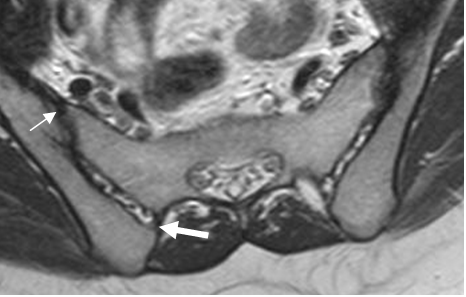

RM axial en T1. Ligamentos sacroiliaco anterior (Flecha delgada) y posterior (Flecha gruesa).